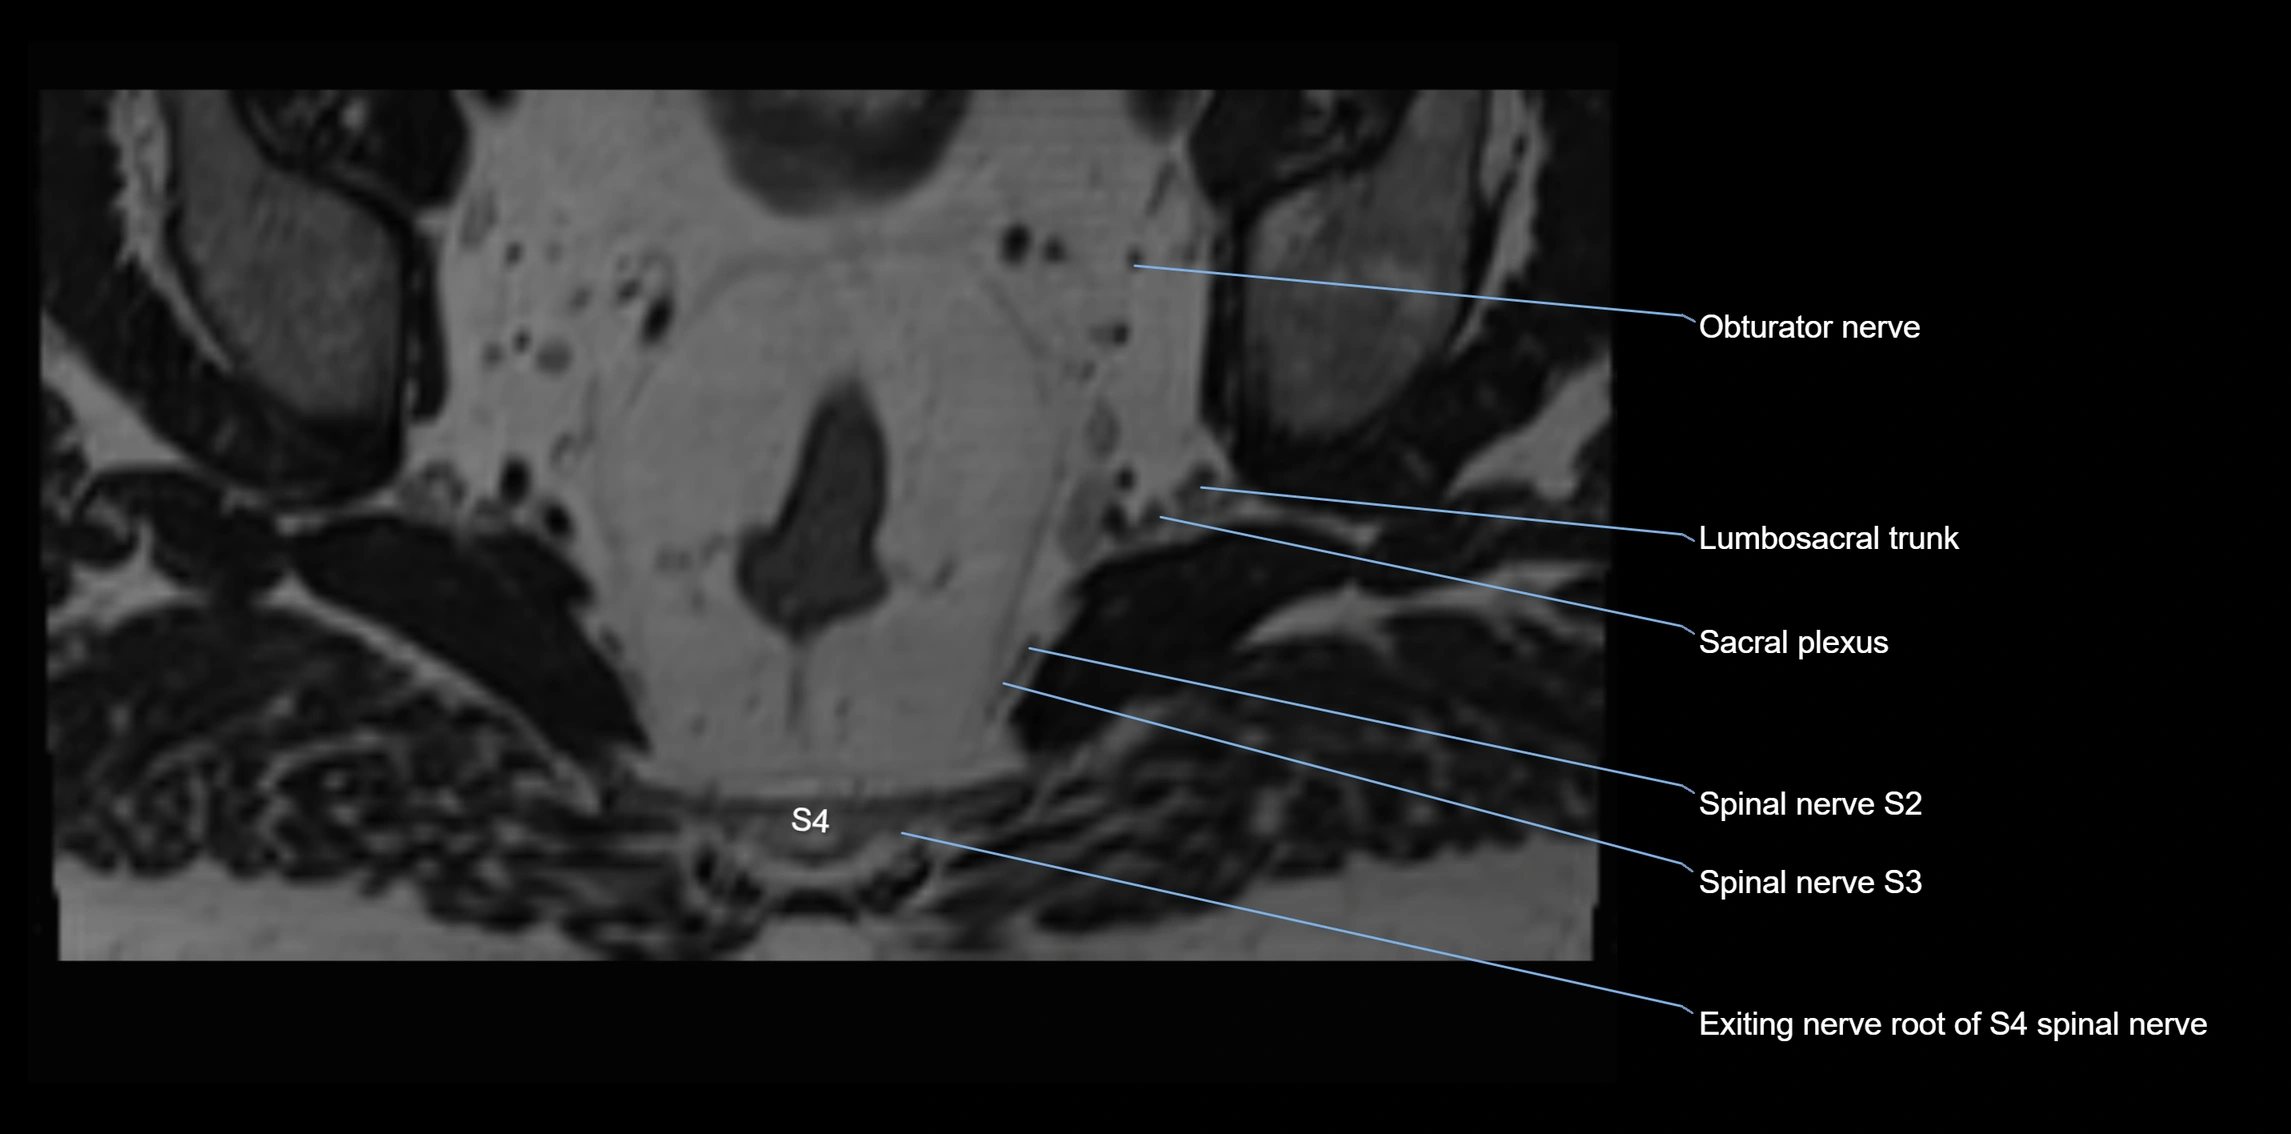

MRI image

image